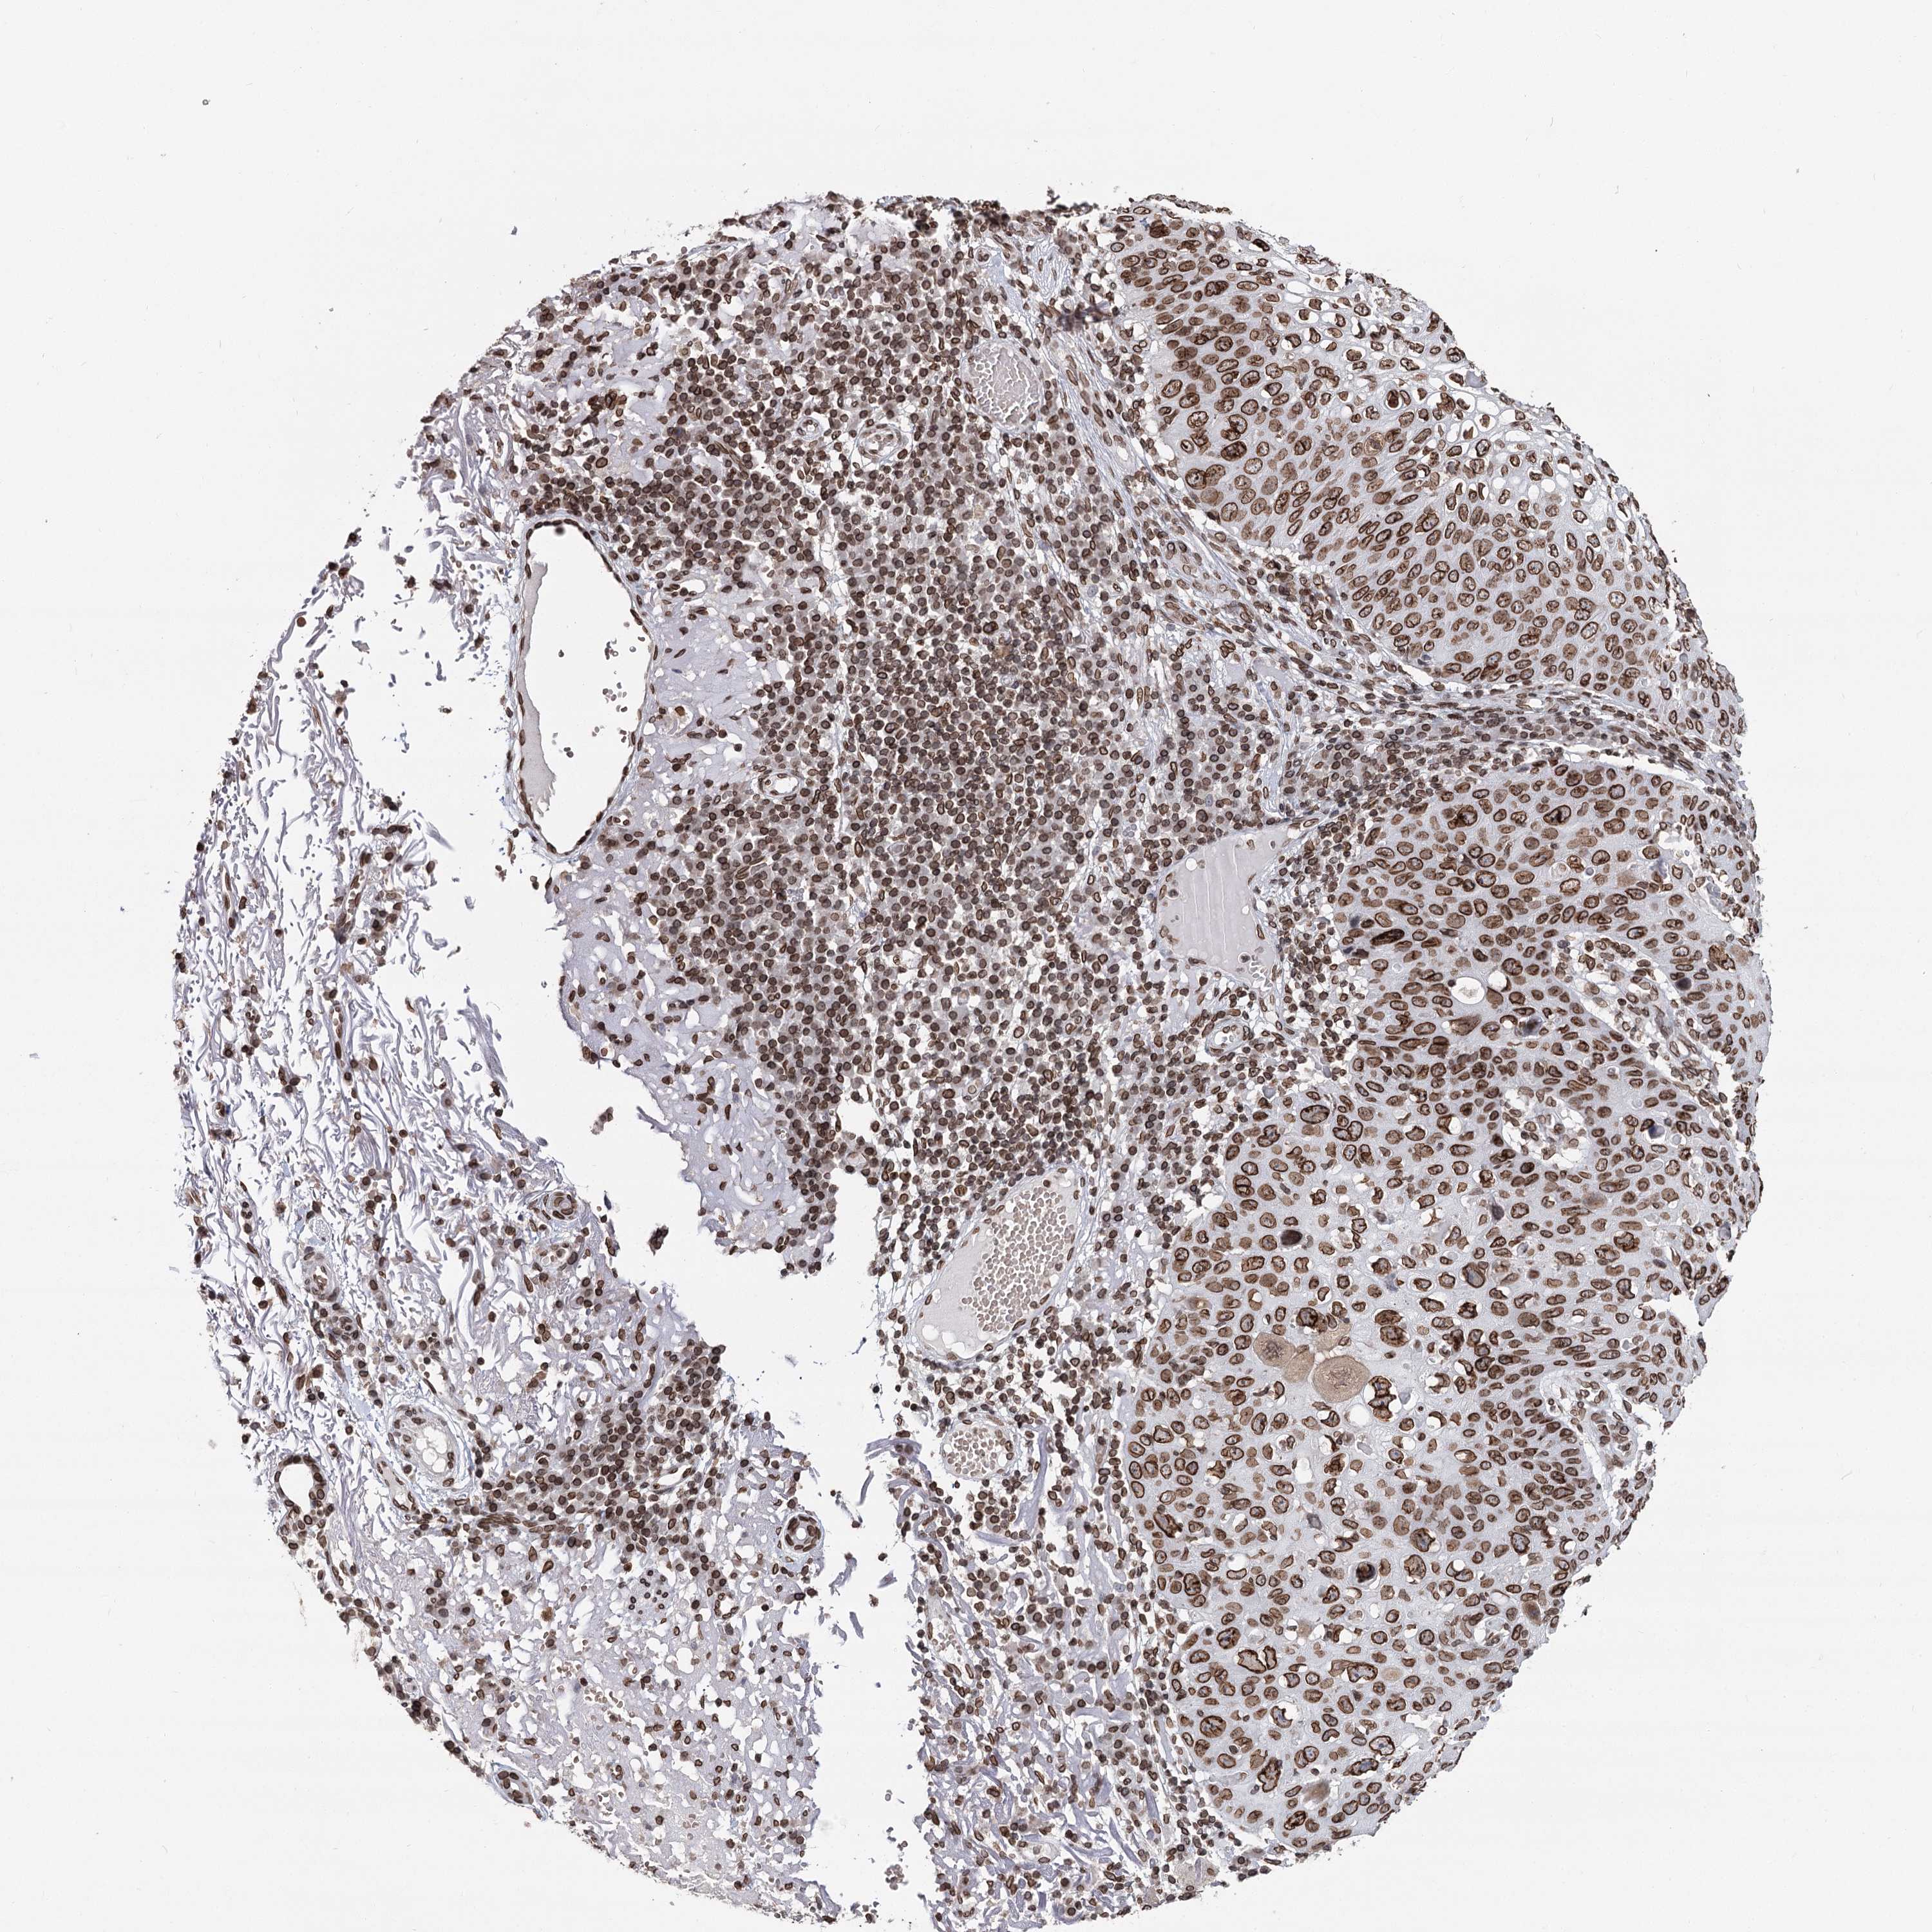

SKIN CANCER - Protein expressioni

A mouse-over function shows sample information and annotation data. Click on an image to view it in a full screen mode. Samples can be filtered based on level of antibody staining by selecting one or several of the following categories: high, medium, low and not detected. The assay and annotation is described here.

Antibody staining in the annotated cell types in the current human tissue is reported as not detected, low, medium, or high, based on conventional immunohistochemistry profiling in selected tissues. This score is based on the combination of the staining intensity and fraction of stained cells.

Each image is clickable and will lead to virtual microscopy that enables deeper exploration of all samples and also displays staining intensity scores, fraction scores and subcellular localization as well as patient and tissue information for each sample.

Antibody HPA038091

Staining

Medium

Intensity

Moderate

Quantity

75%-25%

Location

Nuclear

Squamous cell carcinoma, NOS